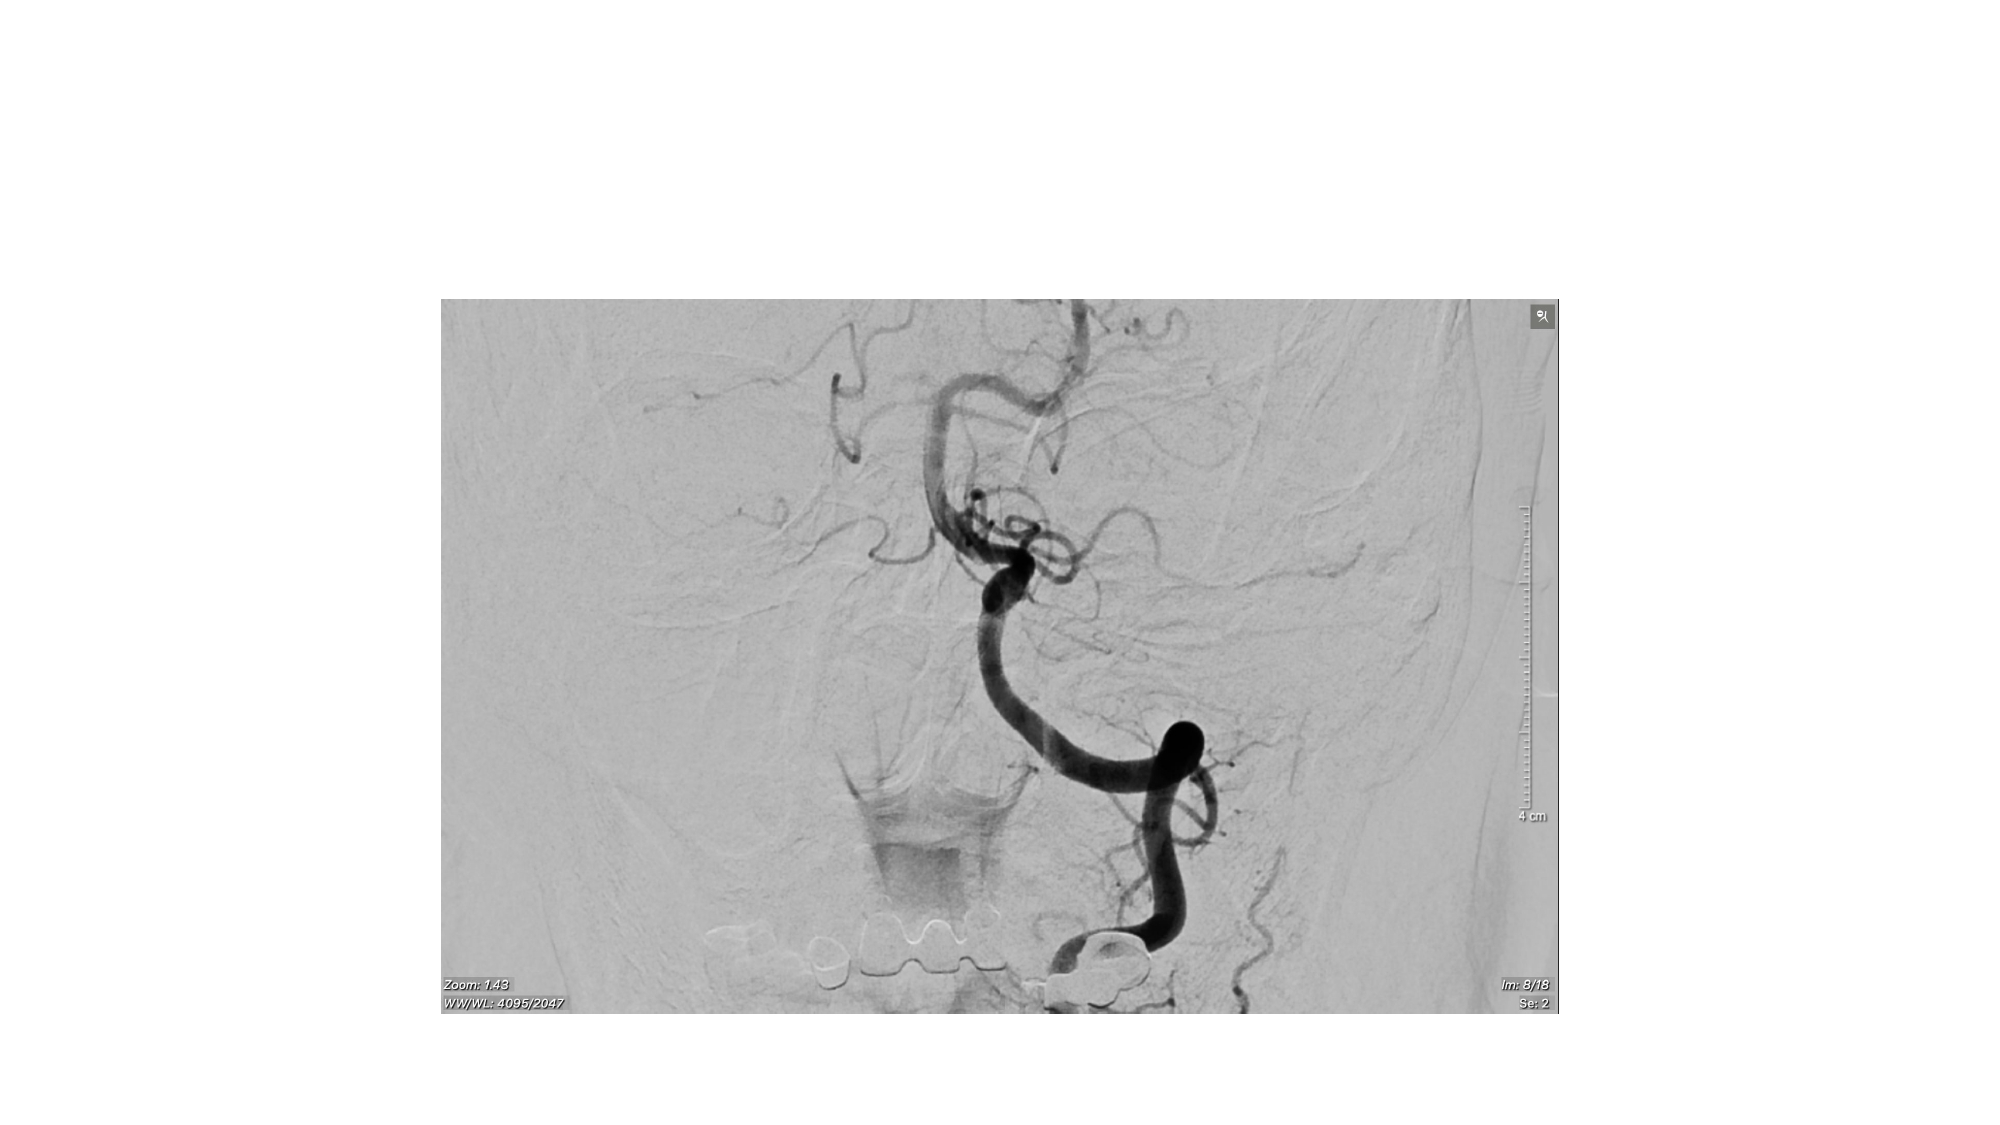

| 13:30 - 14:10 | Surgical management of skull base trauma Endovascular Management of Post-Traumatic Intracranial Vascular Lesions | Assoc. Prof. Nguyen Trong Yen Dr. Nguyen Ngoc Cuong | |

| 15:10 - 16:10 | Interactive Case Demonstration and Discussion II: ~20 minutes each, (5 minutes presentation followed by 15 minutes discussion) Practicals: How I am doing it? Participants present case presentations about how they do it? The faculty comment on and discussion. 1. Endoscopic approach in post-traumatic CSF leakage - Dr. Nguyen Thanh Xuan 2. Endovascular approach in CCF - Assoc. Prof. Le Thanh Dung | Prof. Christian Matula International & local faculties Participants | |